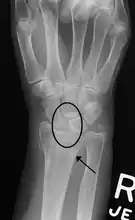

Xray showing a scapholunate dissociation resulting from an injury

It may result from falling on the hand, sprain of the wrist, repetitive motion, or gout.[1][3][5] Diagnosis is based on symptoms, supported by X-rays, MRI, or arthroscopy.[2][6] Injury may be partial (occult) or complete (dynamic or static).[2] X-rays in partial injuries often appear normal, while complete injuries may show widening when the fist is clenched or at rest.[1]

Diagnosis

X-ray images indicate scapholunate ligament instability when the scapholunate distance is more than 3 mm, which is called scapholunate dissociation.[14] A static scapholunate instability is generally readily visible, but a dynamic scapholunate instability can only be seen radiographically in certain wrist positions or under certain loading conditions, such as when clenching the wrist, or loading the wrist in ulnar deviation.[12]